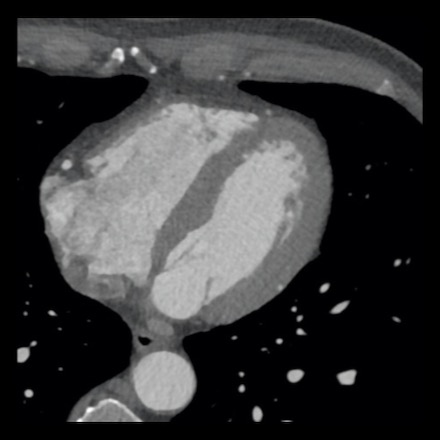

case 4 – CAD-RADS 3/P1/I+ thrombus left ventricle

First, scroll through the CTA images.

How would you describe the findings on the coronary CTA?

The findings are:

- Moderate (50-69%)

stenosis in the proximal LAD caused by a non-calcified plaque. - Variant of

sinoatrial (SA) nodal artery. The artery usually arises from the RCA as a second

branch after the conus artery, however in this case it arises from the LCX,

courses behind the aorta, anastomosing with the right atrium and with a small

branch supplies the SA-node of the heart. - Thrombus in the

apex of the left ventricle. - CTP was performed

in this patient. CTP showed a perfusion defect at stress imaging in the

territory of the LAD (I+), at rest no perfusion defect was visible.

This patient classifies as CAD-RADS 3/P1/I+, which means

this patient requires further investigation.